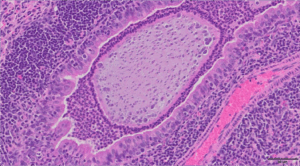

The image above is a representative H&E histological section of a bacteria-laden alginate bead in the airway of a mouse infected with Pseudomonas aeruginosa detected 28 days post infection. Scale bar = 50μm.

This image is from the Wolfgang Lab and was taken by Matthew Greenwald, PhD in collaboration with Alessandra Livraghi-Butrico.